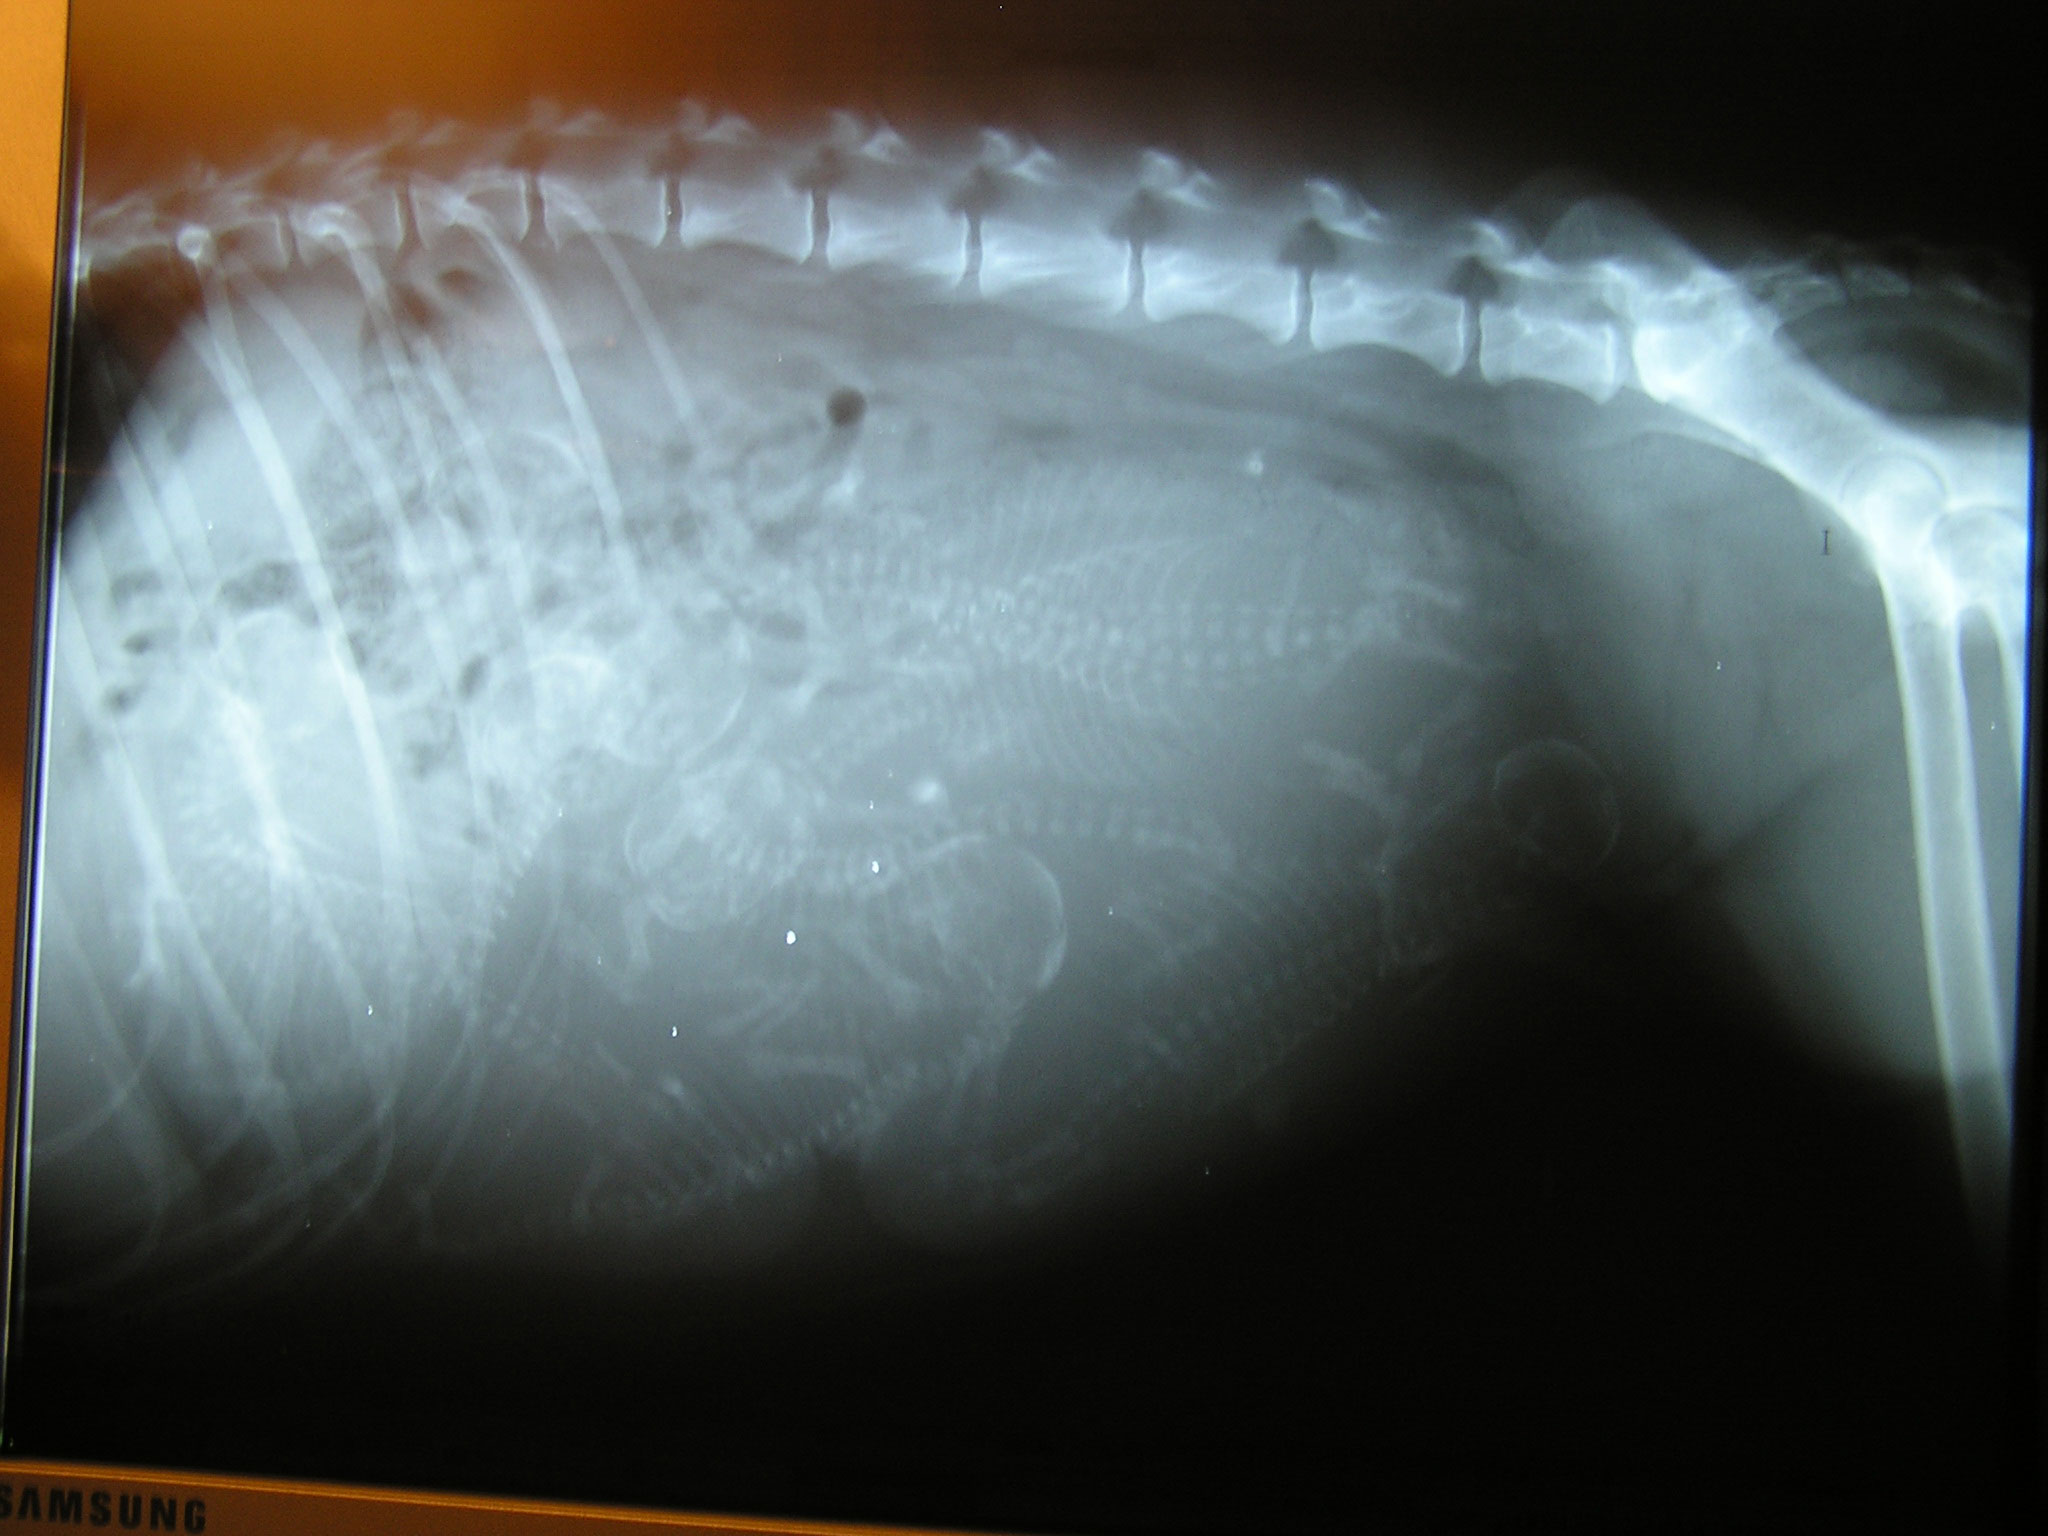

la radio de Tweety à 56 jours de gestation. Vous pouvez

essayer de compter les petits squelettes des bébés pour savoir combien ils

étaient...